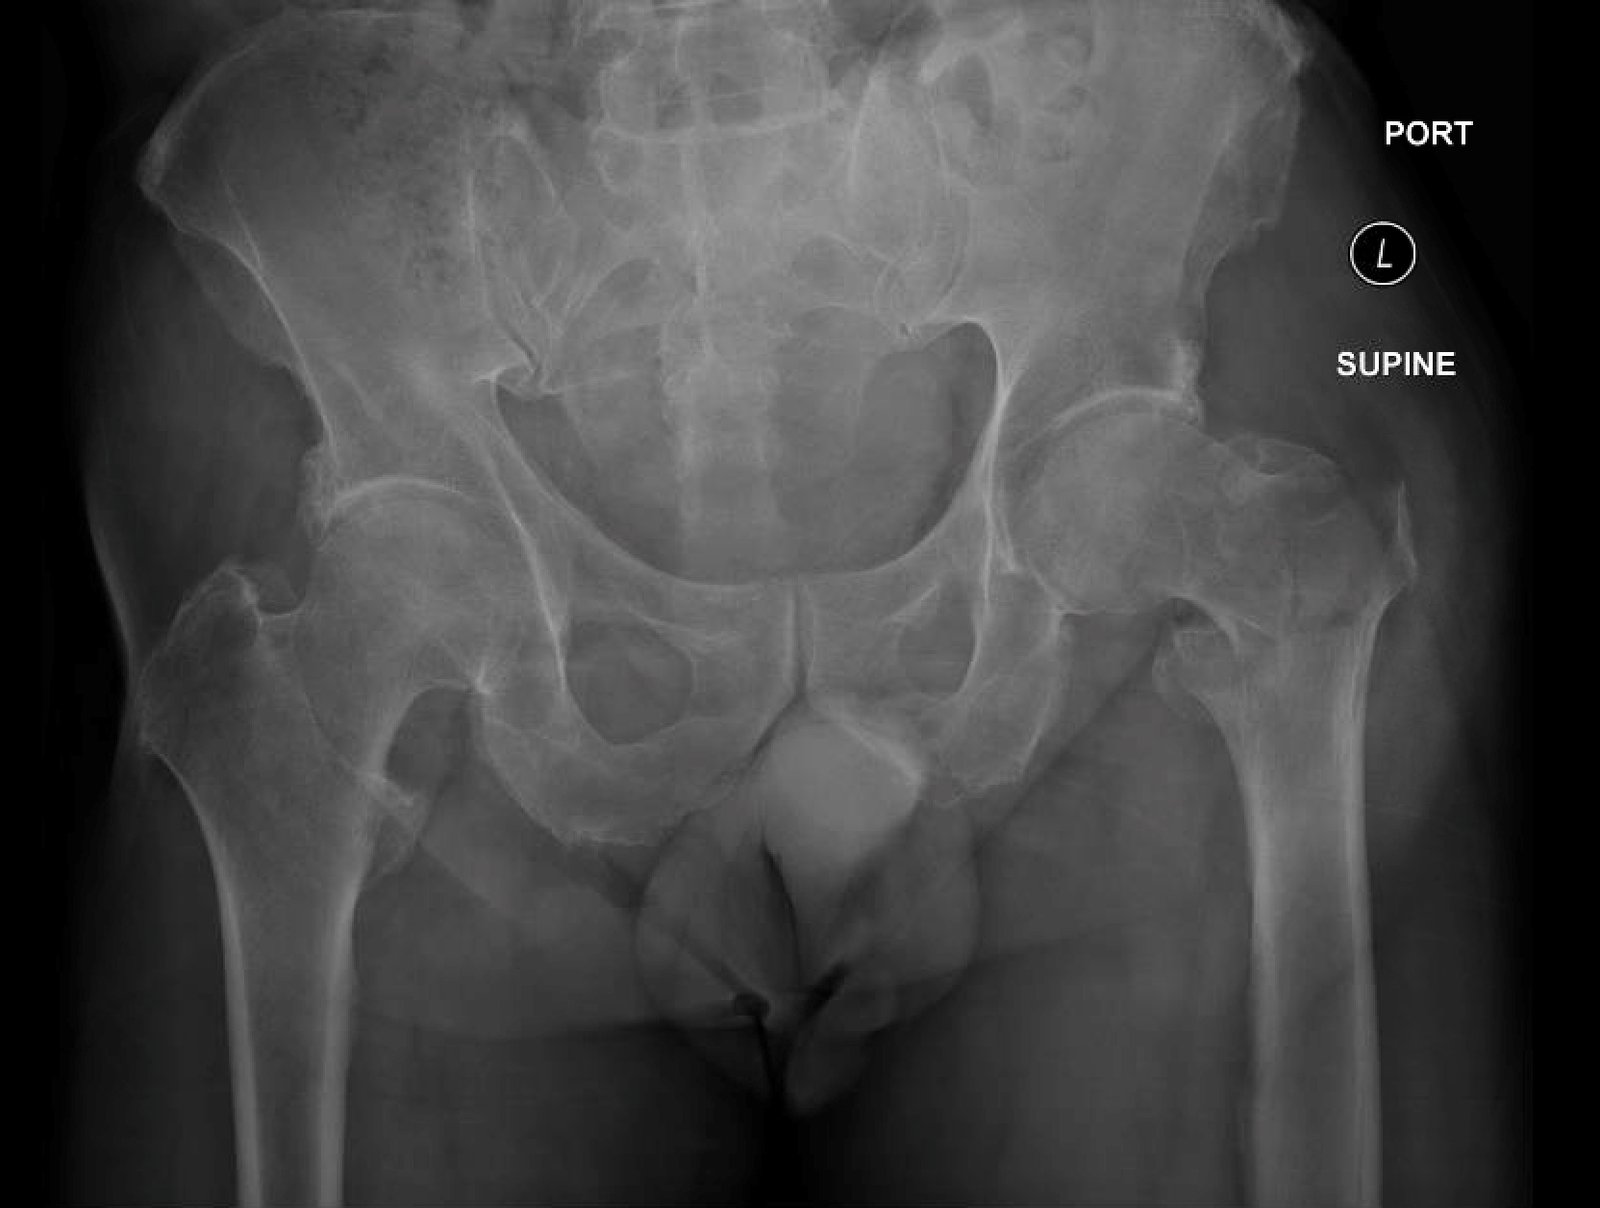

Plain film of the left hip showed acute comminuted displaced intertrochanteric fracture (red arrows) of left femur with varus angulation (green lines) and no dislocation. Greater (blue arrow) and lesser (yellow arrow) trochanters are annotated for reference.

Intertrochanteric (IT) femur fractures comprise around 50% of all diagnosed hip fractures and are considered extracapsular. They most often occur in elderly, female, or osteopenic patients as a result of low-energy trauma, and one-year mortality rates range between 15% and 30%.1,2,3 Patients classically present with external rotation and shortening, and fractures are generally classified as unstable when the posteromedial cortex is disrupted.4,5 Anteroposterior (AP) and lateral pelvis radiographs are first-line while computed tomography (CT), magnetic resonance imaging (MRI), and bone scans are more sensitive secondary modalities.6 Since IT fractures involve vascular cancellous bone, they may cause significant blood loss into the thigh, which may lead to compartment syndrome. Avascular necrosis and malunion have also been described as sequelae of this fracture pattern.7 A thorough integumentary and neurovascular exam is important for any ED provider. Early orthopedics consultation is important because reduction and fixation or arthroplasty are indicated in the majority of operative candidates.4